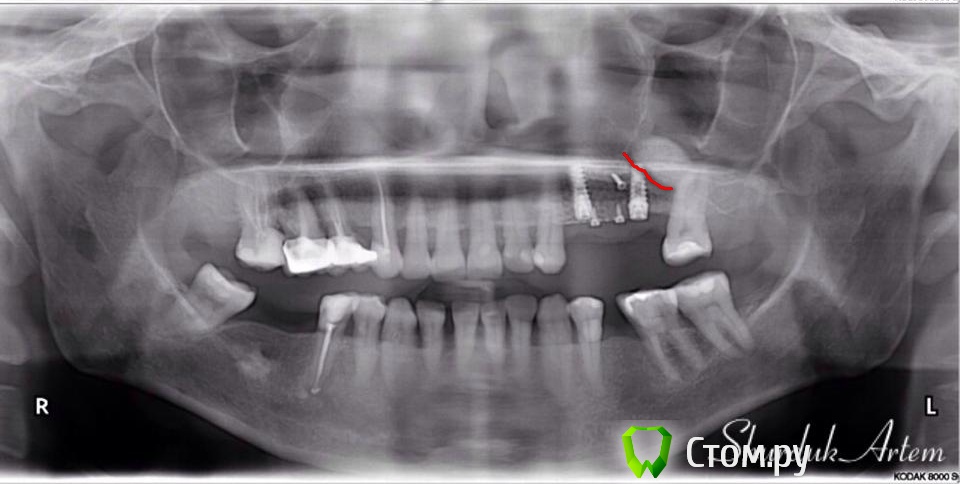

fmn Опубликовано 27 мая, 2014 Автор Поделиться Опубликовано 27 мая, 2014 (изменено) А так. И все же я не согласен. Хорошо. Возможно, здесь вопрос лежит в плоскости механики принятия решений.Представьте себе пациента с вот таким кривым снимком, сделанным на китайском ортопантомографе,по которому даже линию дна верхнечелюстнго синуса тяжело нарисовать с полной определённостью. Пациент отказывается делать КТ. Вы запланируете только имплантацию без синуса и подсадку с резорбируемой мембраной? Изменено 27 мая, 2014 пользователем fmn Ссылка на комментарий